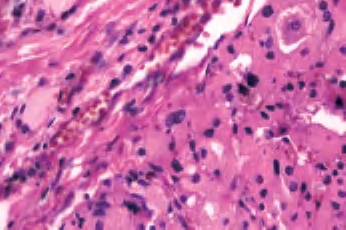

(1)嗜酸细胞腺瘤 单发,界限清楚,包膜完整,具有特征性的红褐色外观,常见中央区瘢痕形成。构成肿瘤的细胞有富含颗粒的嗜酸性胞浆,核大和明显的核仁,胶质常浓染并可形成类似沙砾体的结构,局部可见到乳头结构(图3-32至图3-34)。

图3-34 嗜酸性细胞腺瘤